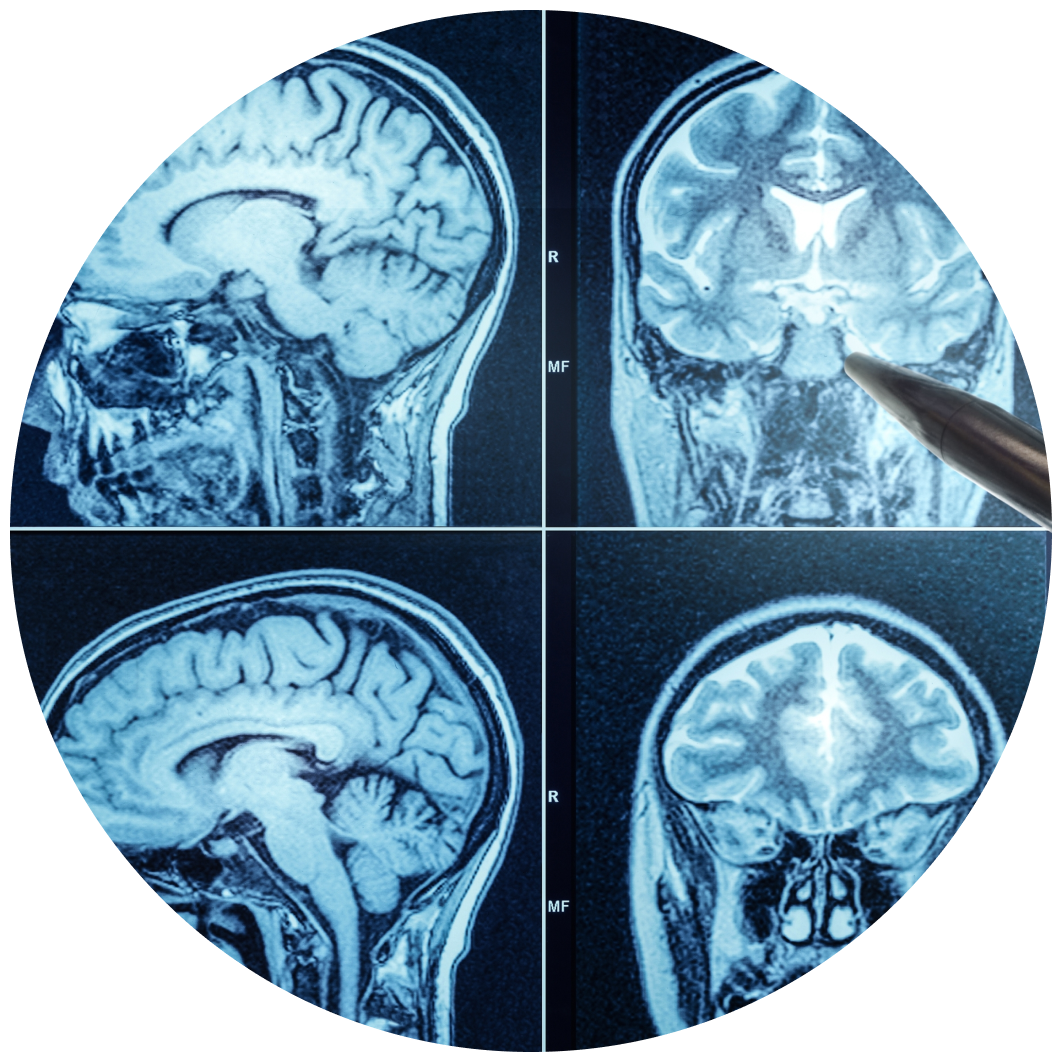

Although Depo-Provera has long been promoted as a safe and convenient birth control option, a growing number of adverse events have been reported to the FDA in recent years. Recent medical studies suggest that women who use Depo-Provera for more than one year may have a fivefold increased risk of developing meningioma brain tumors.